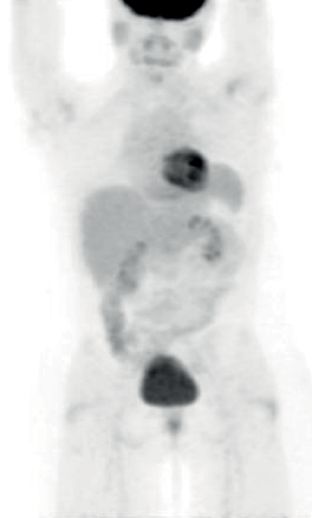

患者4:SQSTM1-NTRK1融合非小细胞肺癌的持久反应

45岁女性被诊断患有IV期NSCLC腺癌,肝脏和纵隔转移以及肥厚性骨关节病(HOA)症状,她曾接受过以前的铂类和培美曲塞治疗。

基因检测发现,NTRK融合基因,接受larotrectinib100 mg每日两次,出现快速反应,表现为第1周期(研究第8天)HOA症状,咳嗽和疲劳的改善以及第3周期完全没有咳嗽。第54天出现部分反应。反应持续时间> 12.88个月。